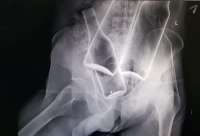

>>6202863 >>6202867 >>6202881 Работа сердца и легких напрямую зависят друг от друга. Тут получается взаимосвязанная цепь пиздеца. Ковид поражает мелкие сосуды, коих дохуя в легких и в голове, это усугубляется холестериновыми бляшками\гипертензией (что встречается у пожилых и жиробасов) В следствии нарушения кровотока в легких падает насыщение крови кислородом, в следствии падения насыщения крови кислородом повышается нагрузка на сердце (оно пытается компенсировать нехватку кислорода повышением частоты сокращений) что вкупе с поражением сосудов легких\сердца еще сильнее пидорасит всю систему насыщения организма кислородом и вызывает застой крови, который приводит к тромбам, инфарктам\инсультам\остановке сердца\усугблению течения сопутствующих инфекций\остановке дыхания

>>6203559 >Лёгкие у них, блядь, слабые? Ну вообще-то да. Там жизненная ёмкость ниже, нижние отделы хуже вентилируются, дыхательная мускулатура слабее из-за избыточного веса.

Когда вентилируешь жиробаса, это целое приключение. И пневмонии у них текут куда тяжелее, чем у нормальных людей. Что в первую очередь связано с тучностью, а не с возможными (но далеко не обязательными) проблемами с сердцем. И мрут от ковидлы жиробасы по тем же самым причинам. Они вообще плохо переносят пневмонии, тем более вирусные.

Ковид в первую очередь - вирусная пневмония. Изначально компрометированные лёгкие переносят её хуже. У жиробасов лёгкие компрометированы всегда из-за конституциональных особенностей. Поэтому жиробасы умирают от ковида чаще.

>>6204808 Подожди, не ты ли пиздел выше (и правильно делал) что мол всё единая система: и лёгкие и сердце и сосуды и всё остальное? >Изначально компрометированные лёгкие переносят её хуже. Изначально компрометированная кардиоваскулярная система тоже хуже переносит вирусные пневмонии при даже идеальных лёгких, статистика есть. Прикол в том что у жиробасов сердечные дела встречаются КУДА чаще лёгочных, наперекор тому что ты затираешь.

Алсо данный микро макрочелик скорее всего откинулся не от пневмопыни, а от тромба. Корона пиздец как начинает ебашить тромбы по кд, это одна из основных опасностей отъезда малоподвижных (молодых в том числе) людей от китайско-уханьского биооружия.

Так что мотайте на ус, детишки, если вы или ваши родственники заболели коронавирусаем, то ебашьте аспирин и другую разжижающую кровь хуйню - поможет не отъехать как жирнич.